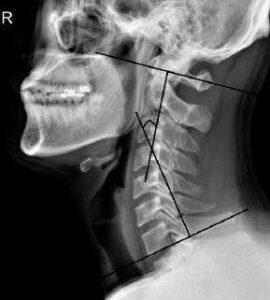

척추는 하나의 유기체입니다. 따라서 허리가 문제라면 이에 대한 반응은 하지, 목, 머리, 팔 등 어느 곳이나 영향을 미치게 됩니다. 허리 디스크가 있었다면 목도 같이 문제가 있다고 보는 것이 더 적극적인 사고입니다. 예전에 허리 디스크 수술해서 허리가 다 나았는데 목디스크가 생긴 경우가 적지 않습니다. 심지어는 동시에 발견되는 경우도 적지 않습니다.